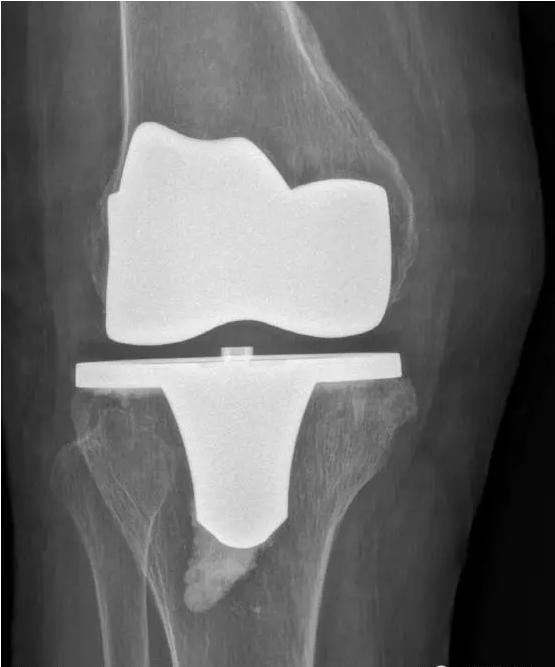

针对晚期(重度)骨关节炎,保守治疗无效时,要积极考虑手术治疗。目前效果最佳的手术方式即为关节置换手术,其他手术方式如关节融合手术等效果较关节置换术相差较大,已不在临床广泛使用。关节置换手术的目的是缓解患者疼痛,矫正关节畸形,恢复关节功能,恢复正常生活。针对老年人来说,积极的手术治疗可以有效恢复其日常生活,避免因疼痛及活动障碍导致患者扶拐或坐轮椅,有效减少因缺乏运动导致的心肺功能障碍及精神问题发生。经过几十年的发展,目前关节置换技术已十分成熟,临床上目前采用的微创技术,手术创伤小,术中出血非常少,术后第二天患者即可下地行走,三月之后即可恢复正常生活及功能。至于人工假体使用寿命,目前进口关节多为20-30年,能满足60-70岁患者的需求。需要关注的是,在行关节置换手术之后,患者仍需要进行积极的康复治疗,包括关节活动度及周围肌力的锻炼等,这样才能达到最佳的手术效果。

术后图如下: